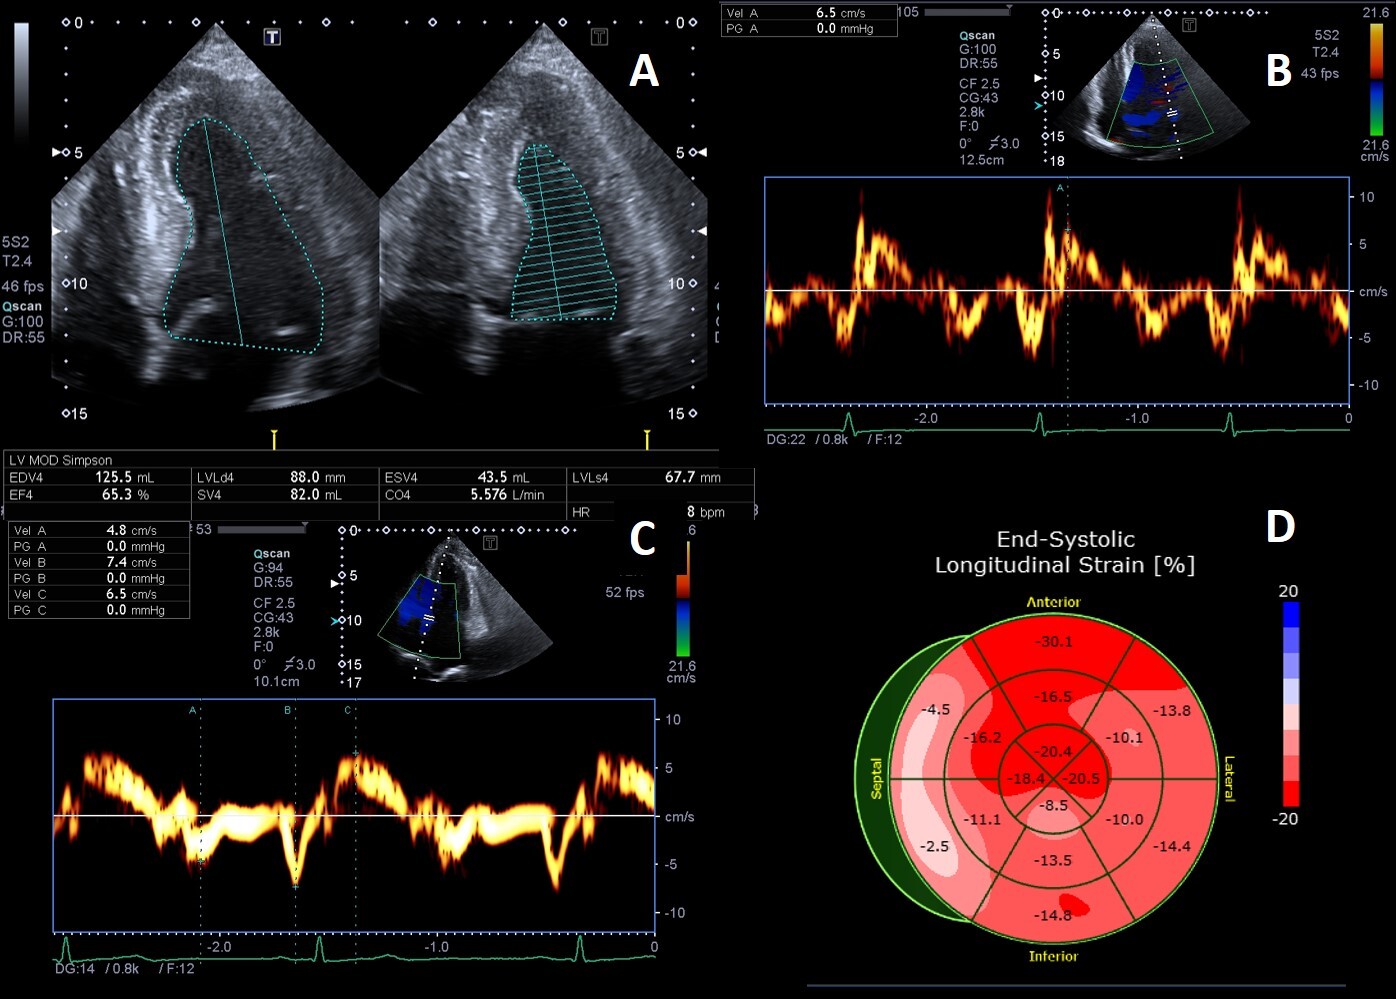

The added value of 3D echocardiography needs to be proved but its strong correlation with CMR for the estimation of LVM and LVEF [103, 104] and for the detailed study of myocardial strain [105, 106] and heart valves [77] (Fig. 5) is promising.

Fig. 5.3D Echocardiography. (A) 3D echocardiography LV-analysis with regional strain analysis mapped onto the LV model and shown in the bull’s eye plot for clear visualization. (B) 3D transesophageal echocardiogram mid-esophageal long axis view. The arrow points to minor chordal rupture and the purple arrows to mild aortic cusps thickening.